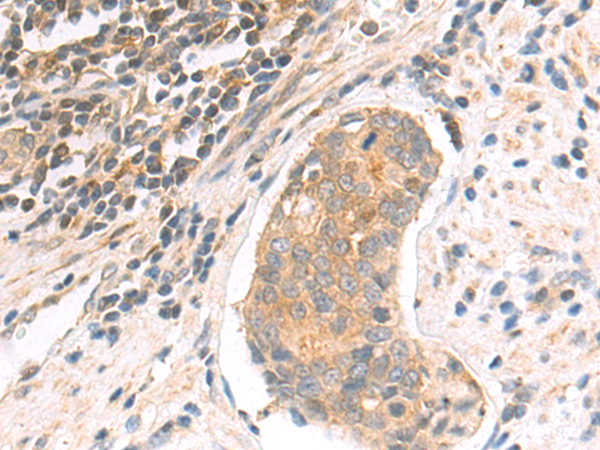

IHC positive control: |

Human lymphoma and human breast cancer |